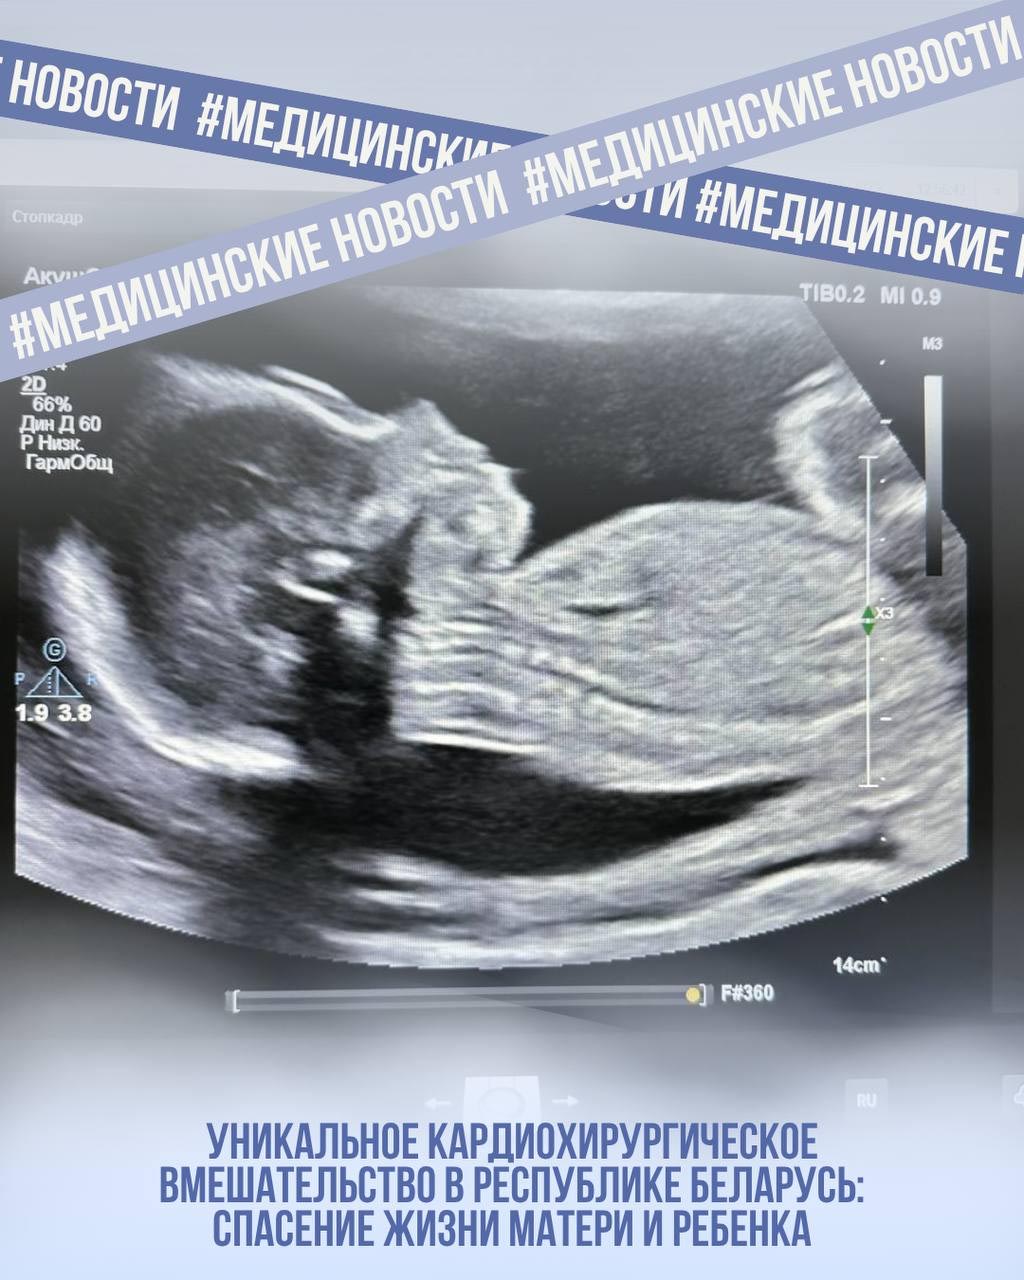

Пациенткой оказалась 33-летняя женщина, находившаяся на 23-й неделе беременности. У нее была диагностирована миксома левого предсердия – доброкачественная опухоль, которая может представлять серьезную угрозу для жизни как матери, так и развивающегося плода.